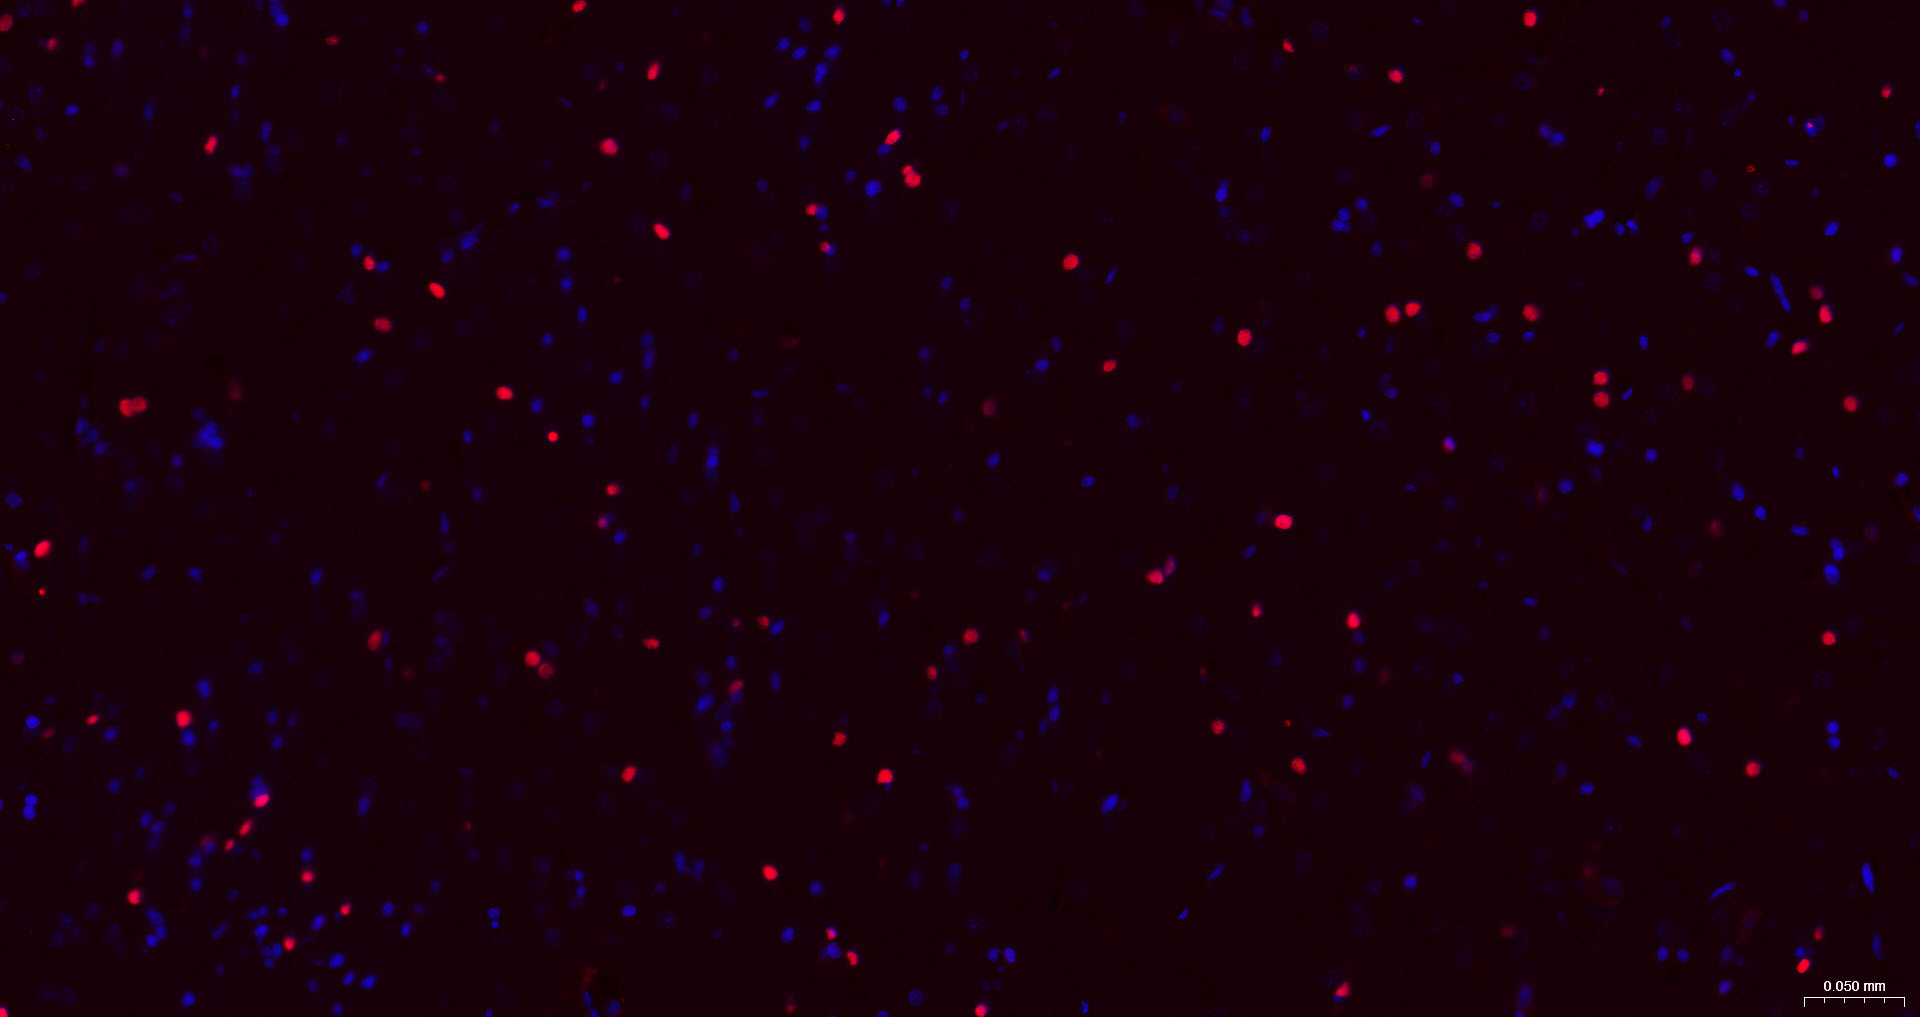

• IF(ICC)

IF(ICC) IFICC1:50-200